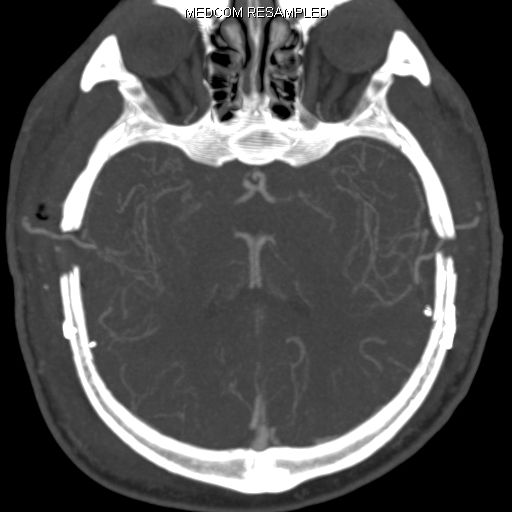

CT Schnittbildgebung

Postoperative CT Schnittbildgebung von beidseitig neu gelegten extrakraniellen-intrakraniellen Bypässen (Gefäße die durch die kleine Öffnung im Schädel hindurchziehen)